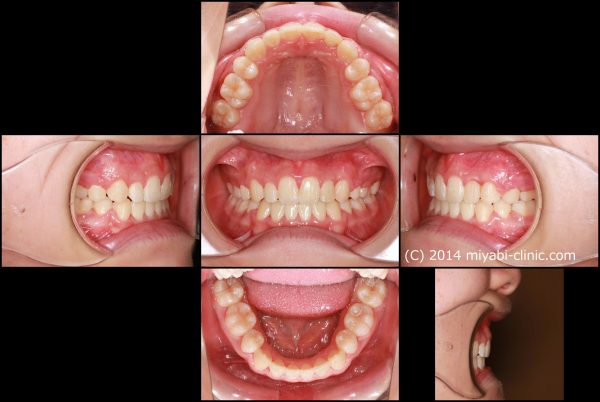

「 八重歯を 治してほしい」 21歳 女性 治療期間19か月(上下顎叢生)

21歳の 女性です。

「 八重歯を 治してほしい 」との事で来院されました。

典型的な ”八重歯” の状態です。

犬歯(中心から3番目の歯)が外に飛び出しています。

この犬歯の影響で口内炎が絶えないのが悩みとの事です

前歯 4本のうち、2本が 逆に噛んでいます

上の八重歯に目が行きがちですが、下の歯ならびも、乱れた状態ですね

犬歯の唇側転位を伴う 上下顎叢生です

八重歯と 口もとを治すために上下顎左右の小臼歯抜歯を行い、前歯を整列しました。

2022年11月28日にスタートして 、2024年5月25日に 終 了 しました。

治療期間は19か月でした。

小臼歯の抜歯を行ったことで 犬歯の飛び出しが整い、

前歯は整列し八重歯はすっかりと解消しました。大きすぎた歯ならびが適正になりました。

上だけ注目されがちですが、下あごも前歯が整列し歯ならびが整いました。

また、前後的な距離が短くなり、適正な長さになりました。

上下の顎が適正な長さになった、この効果で上下の前歯が下がりました。

治療前後で前歯の傾斜、八重歯の飛び出しがかなり改善しました。